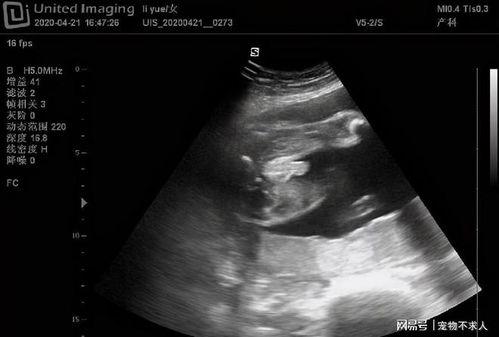

首先,让我们来明确一下什么是阴式检查视频。阴式检查视频,顾名思义,就是通过视频形式展示女性私密部位的检查过程。这类视频通常由专业的医疗机构或医生制作,旨在为患者提供更直观的医学知识,帮助她们更好地了解自己的身体。

这类视频主要针对患者,展示医生进行阴式检查的过程。它们通常包含详细的操作步骤和注意事项,帮助患者了解检查过程,减轻紧张情绪。